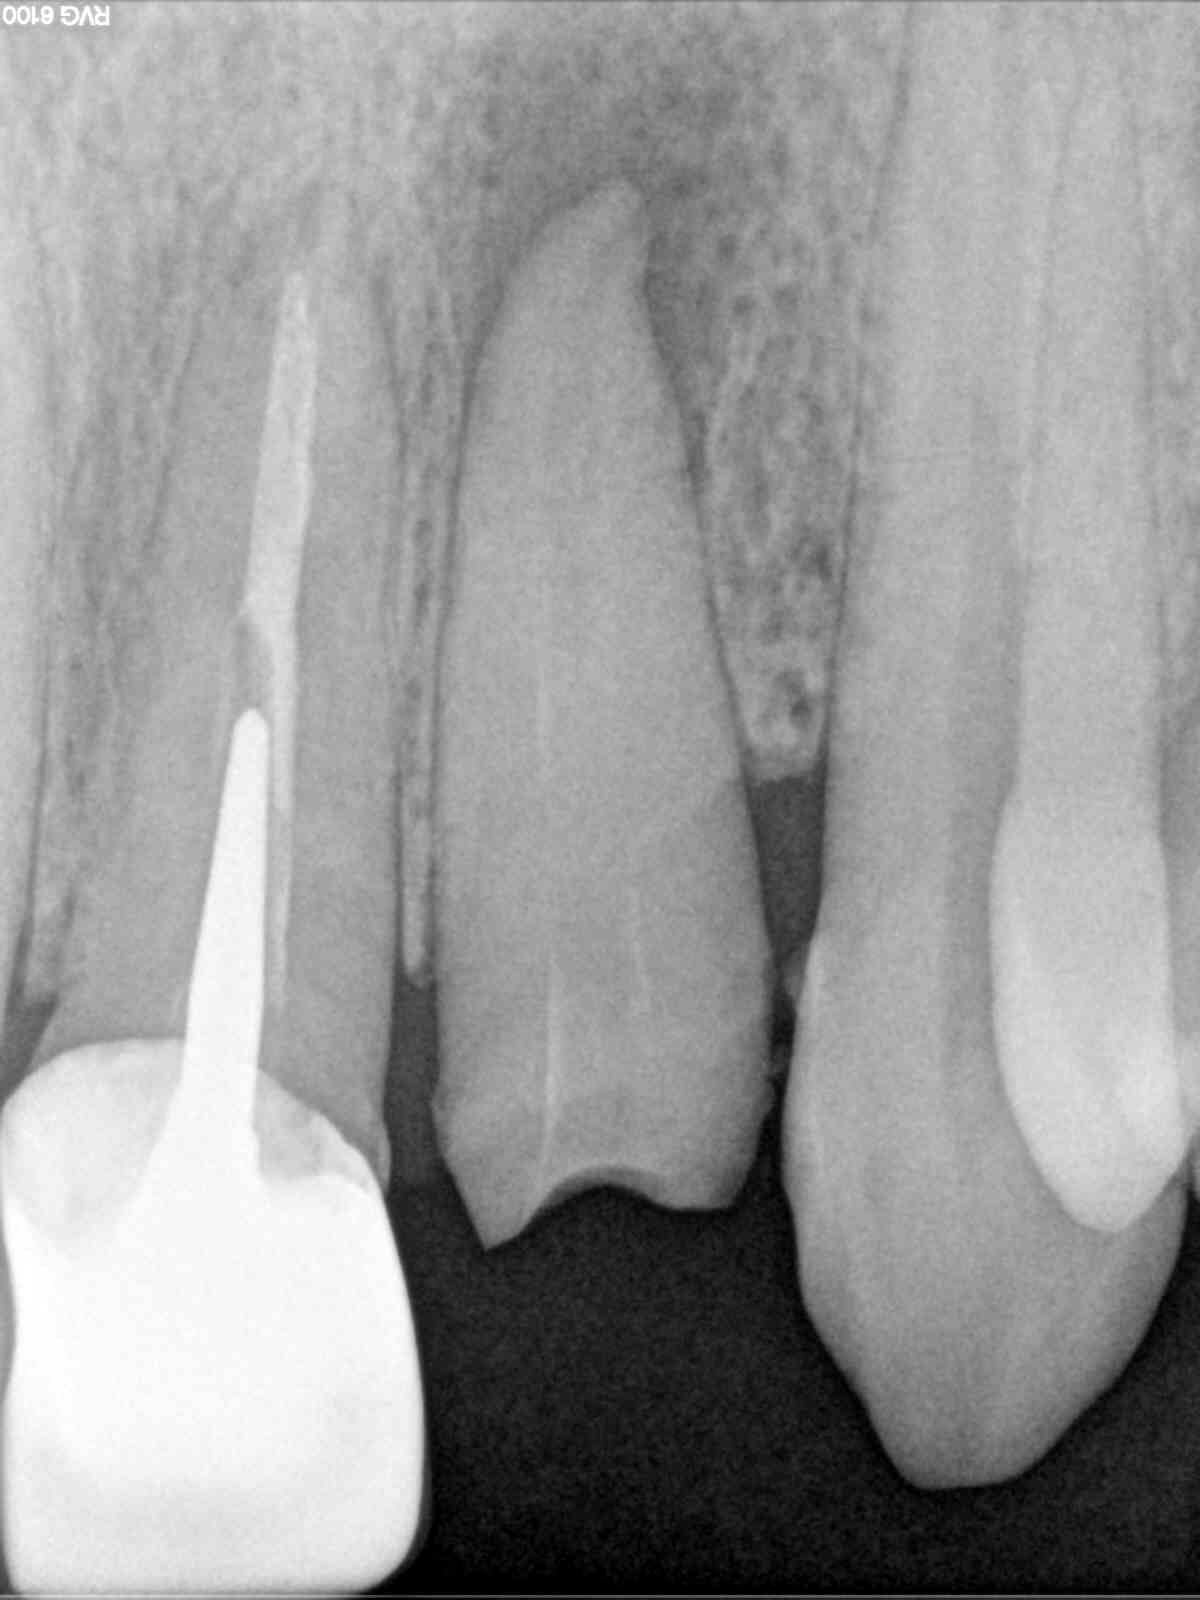

Mon petit cas , une 22 avec un abcès palatin récidivant depuis des années et pour cause ...pas d'obturation sous une couronne , les rd datent de début décembre , fin janvier , fin mai . tutti va bene , plus de trace de rien au palais

Alors j'ai fais l'endo début janvier , ça allait mieux , mais il restait toujours une petite tuméfaction au palais , je me suis dit vas-y casa tu l'as déjà fait ...! donc fin janvier , j'ai extrait le dent , retouché un peu l'apex , un petit crochet inesthétique ! ,cureté le fond de l'alvéole ..et j'ai remis avec une provisoire sans contention rien ... j'ai vérifié en Mars je crois , tout allait bien , plus rien au palais , en mai j'ai fait la définitive ....impeccable ! aucune mobilité gencive impeccable !

La radio initiale .